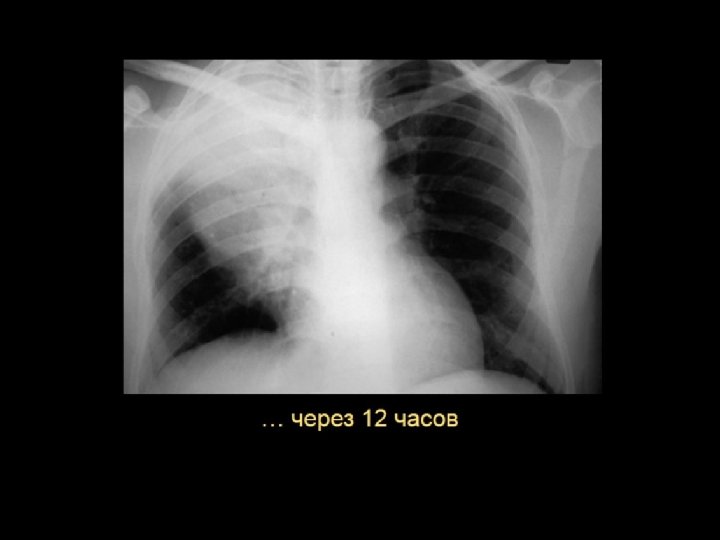

Однако …. l У больных пожилого возраста респираторные симптомы в начале заболевания могут отсутствовать, а на первый план – сонливость, спутанность сознания, нарушения сна, снижение аппетита, обострение/декомпенсация хронических заболеваний (в 45%) l У 20% больных объективные симптомы пневмонии могут отличаться от типичных или вообще отсутствовать l Изменение классической картины заболевания, так как минимум 30% больных до поступления в стационар принимают антибиотики l Поэтому актуально своевременное проведение рентгенологического исследования (в 2 -х проекциях) 6